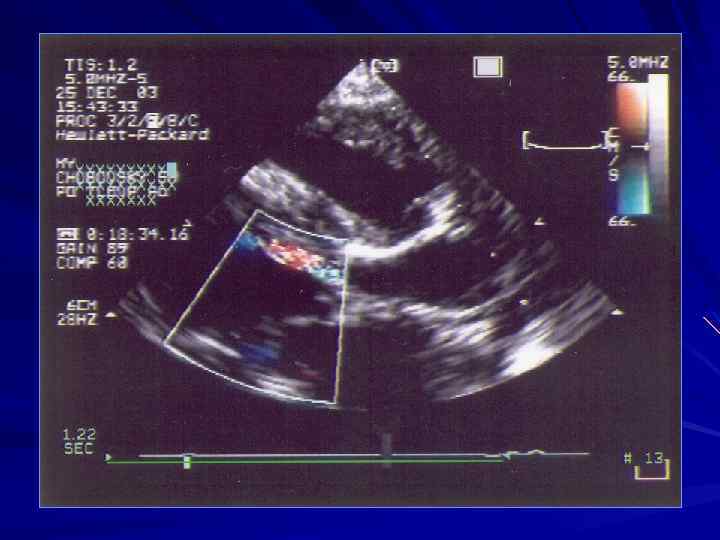

Эхокардиографические признаки аортальной недостаточности несмыкание створок в диастолу систолическое дрожание створок АК. Не является специфическим признаком. Встречается в норме. диастолическое дрожание ПС МК дилатация левых камер сердца и сферическая форма ЛЖ наблюдаются у больных в том случае, если аортальная регургитация превышает I степень. диастолическая реверсия потока в брюшном отделе аорты и в грудном нисходящем отделе аорты

Аортальная недостаточность I степень непосредственно под створками АК; II степень - до конца передней створки митрального клапана; III степень - до концов папиллярных мышц; IV степень - до верхушки левого желудочка

Аортальная недостаточность

Аортальная недостаточность Критерии оценки степени аотальной регургитации по величине vena contracta: v. с. < 3 мм – незначительная 3 6 мм – умеренная > 6 мм – значительная

Для оценки значимости аортальной регургитации используют показатель времени полуспада градиента давления (РНТ). Для этого трассируют по контуру склон EF потока аортальной регургитации. Если РНТ > 400 мс, степень регургитации, как правило, незначительная или умеренная; если РНТ < 200 мс, степень регургитации значительная или высокая и она гемодинамически значима. когда показатель РНТ равен 300400 мс, оценивают степень дилатации левых отделов сердца и степень нарушения систолической функции ЛЖ.